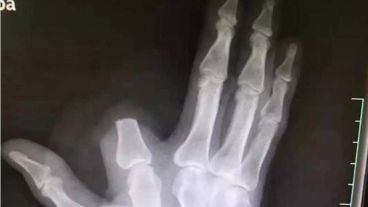

Un vecino de una zona rural y montañosa del distrito de Shangyu, en la provincia china de Zhejiang, se amputó un dedo de la mano tras ser mordido por una serpiente venenosa. Acto seguido se dirigió al hospital y los doctores le indicaron fue un acto innecesario y no pudieron someterlo a un reimplante.

Según publicó ActualidadRT, el hombre sin dudarlo y para evitar que el veneno se propagara por su organismo, se cercenó su dedo índice separando la parte donde fue mordido del resto de la mano. Acto seguido, envolvió la herida y se dirigió al hospital más cercano, ubicado a 80 kilómetros de distancia en la ciudad de Hangzhou.

Zhang fue tratado por sus heridas y se encuentra recuperándose en su casa, aunque lamentablemente no pudo recuperar su dedo, ya que al apresurarse a al hospital se olvidó de recoger la extremidad amputada en la montaña.